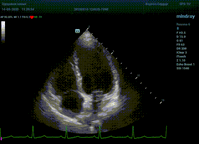

Что могут предложить современные приборы? Приборы нашего времени являются мощными вычислительными машинами, способными обрабатывать полученную информацию даже без помощи человека. Система автоматического вычисления фракции выброса – AUTO EF на приборах серии Resona компании Mindray сделает все за вас. За пару секунд прибор сам отыщет нужную фазу сердечного цикла и произведёт измерение и расчеты, а также покажет график изменения объема в сердечном цикле. От Вас требуется только получить качественное 4С и 2С сечение. Впрочем, прибор всегда оставляет возможность коррекции, если доктор имеет свое мнение на расположение точек планиметрии или момента измерения по ЭКГ каналу.